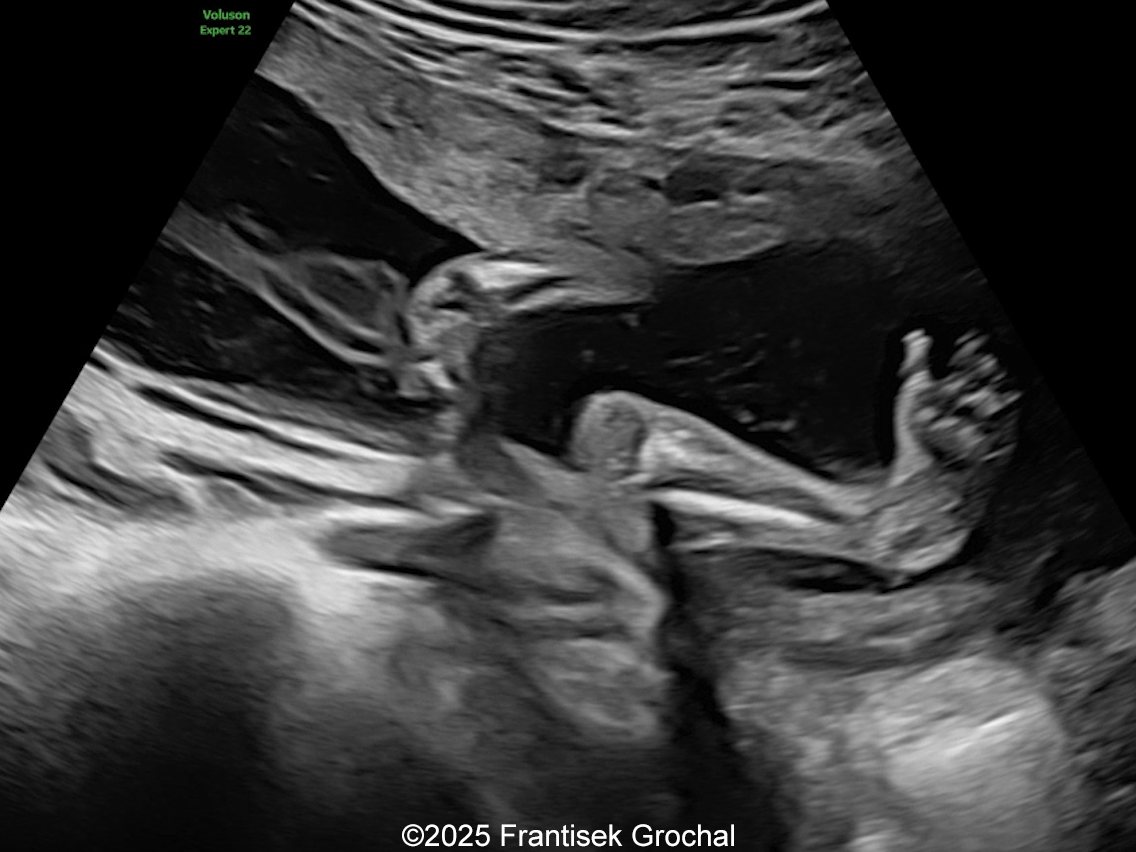

We present a case of Amniotic Band Sequence seen in 21st week of pregnancy. The fetus showed the following findings:

- Bilateral club feet

- Constriction of the right thigh by the amniotic band

- Constriction of fetal torso by two strips of amniotic band